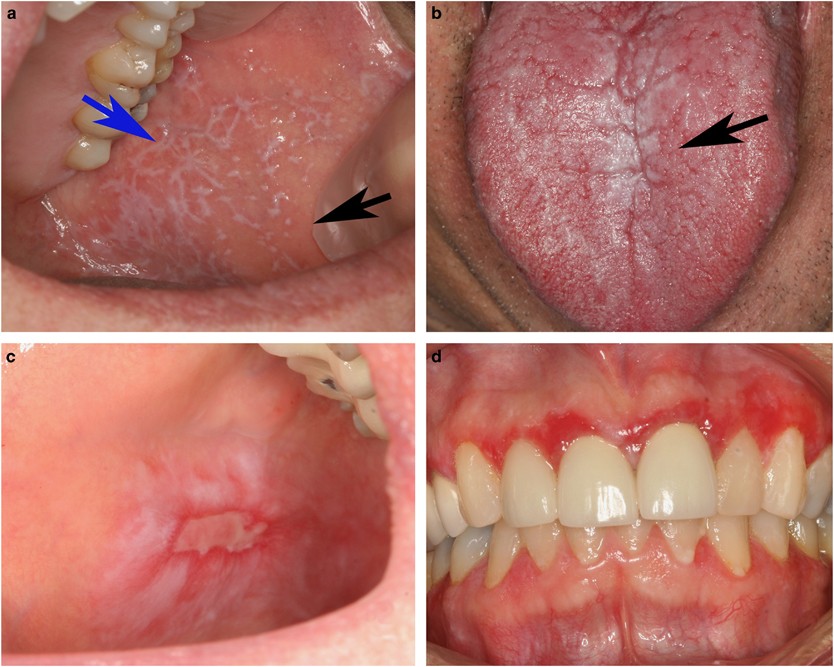

Oral Lichenoid Lesions Distinguishing The Benign From The

Oral Cancer And Potentially Malignant Disorders Intechopen

Oral Cancer And Precancerous Lesions Neville 2002 Ca

Carcinoma In Situ Of Oral Cavity Dermnet Nz

Oral Cancer And Precancerous Lesions Neville 2002 Ca